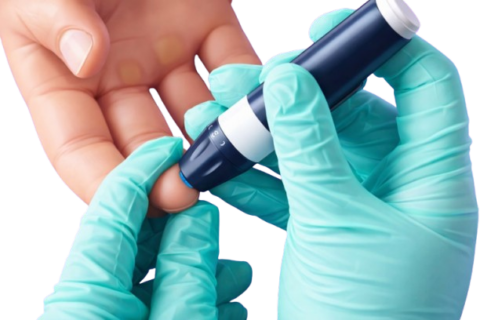

The International Diabetes Federation (IDF) officially recognized a fifth form of diabetes in 2025, after decades of controversy. It’s now urging other health authorities, like the World Health Organization (WHO), to follow suit. Type 5 diabetes is…